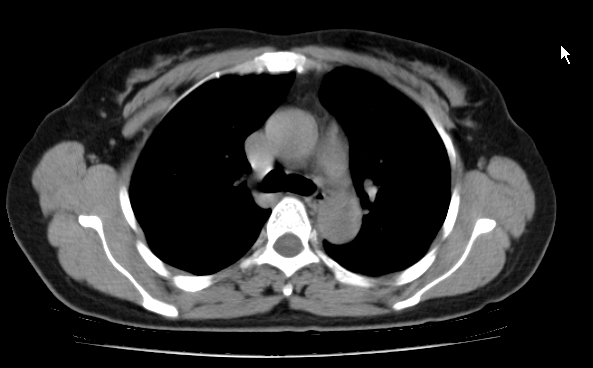

标题: CT25227:背部疼痛伴双侧胸壁痛2月,食欲差。 [打印本页]

标题: CT25227:背部疼痛伴双侧胸壁痛2月,食欲差。

肺结核并胸椎结核?请各位高手指教。

用椎体的条件来扫胸椎呀!考虑1左侧胸膜小结节形成2椎体结核并冷脓肿形成

考虑胸椎结核并椎旁软组织肿胀。

左肺结核灶,胸椎结核并冷脓肿。

支持!不排除骨原发淋巴瘤肺内转移。

食道癌并胸椎及肺内转移